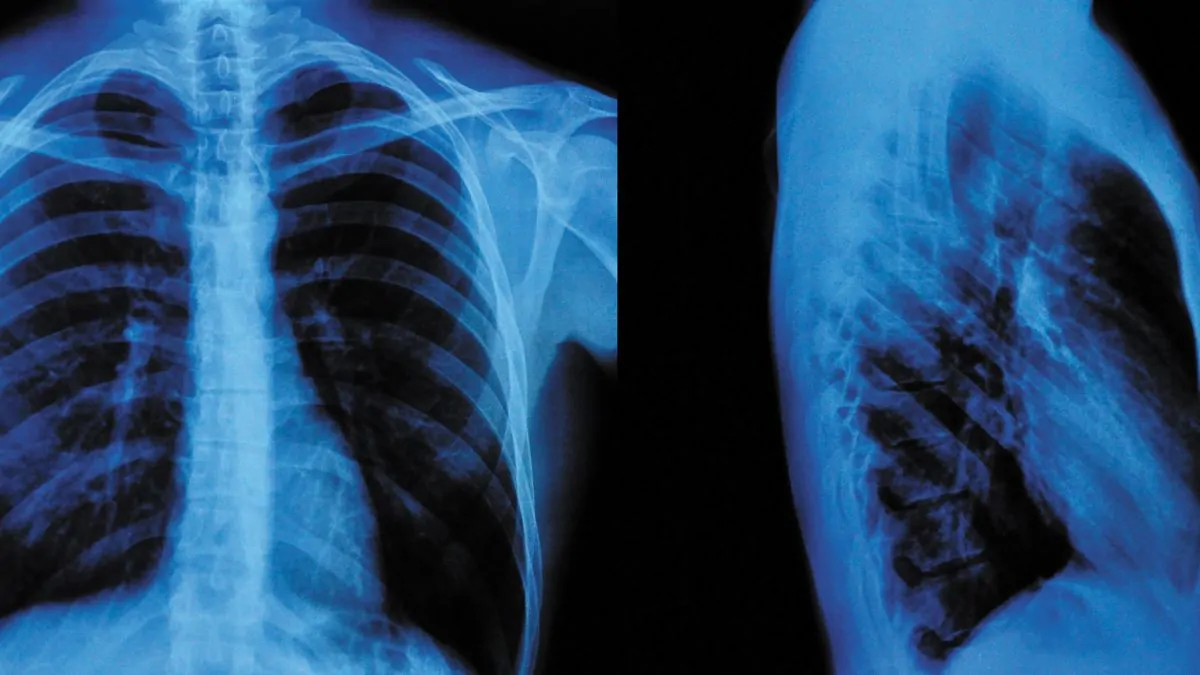

En la intersección entre la tecnología y la medicina, la inteligencia artificial (IA) está revolucionando la forma en que se realizan diagnósticos, especialmente en áreas como la radiología, donde la carga de trabajo y la escasez de profesionales son desafíos constantes. Un reciente estudio publicado en Radiology ha arrojado luz sobre el potencial de las herramientas de IA para descartar patologías en radiografías de tórax, ofreciendo una precisión comparable, e incluso superior, a la de los radiólogos humanos en ciertos casos.

El estudio, llevado a cabo por un equipo de investigadores en Dinamarca, incluyó datos de 1.961 pacientes con una edad media de 72 años. Los investigadores analizaron radiografías de tórax obtenidas en cuatro hospitales, con el objetivo de determinar si la IA podía excluir correctamente la patología en imágenes sin aumentar los errores de diagnóstico. El enfoque principal fue comparar la calidad y la gravedad de los errores cometidos por la IA frente a los radiólogos.

La herramienta de IA utilizada en el estudio fue capaz de excluir correctamente la patología en un rango del 24,5 % al 52,7 % de las radiografías no destacables, manteniendo una sensibilidad superior al 98 %. Lo más sorprendente fue que las tasas de errores críticos de la IA fueron menores en comparación con los informes radiológicos tradicionales. Sin embargo, el Dr. Plesner destacó un punto crucial: “Los errores cometidos por la IA fueron, en promedio, clínicamente más graves para el paciente que los errores cometidos por los radiólogos”.